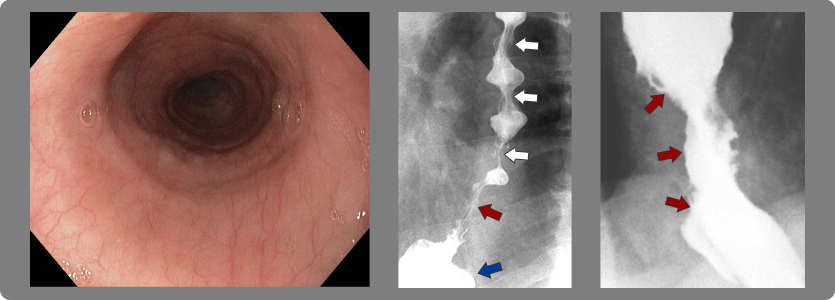

2- Estrechez (estenosis) del esófago

Cuando la esofagitis es grado C o D se producen múltiples cicatrizaciones de la pared y eso origina retracción de la misma con la consiguiente estrechez del esófago y dificultad para tragar (disfagia).

Flechas blancas: ondas terciarias de esófago

Flechas rojas: áreas de estrechez esofágica

Flecha azul: hernia hiatal